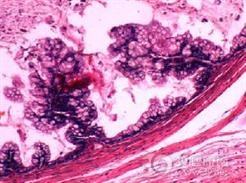

乳腺叶状囊肉瘤的病理特点为:

1.大体形态 肿瘤体积差别较大,小的直径2~3cm呈结节状,大者可为40~50cm的巨块,恶性肿瘤又较良性瘤体积略大。肿瘤边缘也较清楚,无真正的包膜。切面呈灰白色,在坏死区或脂肪肉瘤瘤样变区则带黄色。约1/3的病例肿瘤有囊腔,囊内有清澈或血性液体。更常见的是多个息肉状肿物充塞了囊腔,造成肿瘤切面的裂隙状态。肿瘤质软如肉,其中也有较硬的部分,有时可有骨和软骨化生。

2.组织形态 瘤组织由上皮细胞和纤维组织两种成分构成,只是纤维组织成分增生更加活跃,构成肿瘤的主要成分。细胞排列密集,核肥大深染,似纤维肉瘤或低度恶性纤维肉瘤。在同一肿瘤中的不同切片,或同一切片的不同区域纤维细胞的密度和分化程度可以很不相同。少数病例间质成分中尚可发现分化程度不同的脂肪组织,黏液组织,甚至软骨等。诊断本病除上述成分外,必须发现有上皮细胞成分,否则和乳腺肉瘤难于区别。